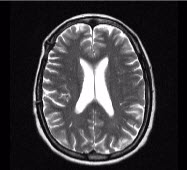

Magnetic Resonance Imaging MRI

MRI 2

MRI Sequences